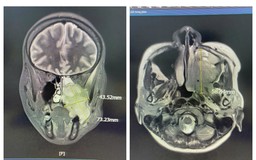

Vỡ sọ, dập não sau xô xát, nam thanh niên được cứu sống đầy ngoạn mục

Vài ngày sau cuộc xô xát, tưởng chừng đã bình phục thì nam thanh niên 35 tuổi bất ngờ đau đầu dữ dội, rối loạn hành vi và được đưa đến cấp cứu tại Bệnh viện Đa khoa Quốc tế Nam Sài Gòn. Kết quả chẩn đoán khiến ai cũng bất ngờ: sọ trán lún hai bên, não dập xuất huyết nặng - cần được phẫu thuật khẩn cấp.